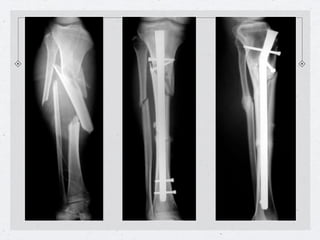

Clavo centromedular de tibia

Curvatura adaptada

Clavo hueco

El enclavado endomedular en fracturas cerradas de diáfisis

permite la reducción de todos los desplazamientos, ¿excepto

uno, cual?, ¿como solucionar este inconveniente?

- Un clavo centromedular no

siempre bloquea la rotación ( solo

cuando los dos fragmentos fueron

fresados en una longitud

suficiente).

- La solución es bloquear el clavo al

hueso, mediante tornillos

transversales.

Enclavado de tibia en fractura cerrada

Clavo sin Bloqueo   Clavo con Bloqueo con aletas   Clavo con Bloqueo con Pernos

Callo óseo luego del enclavado

centromedular de tibia a foco cerrado.

Ventajas del

Clavo Centro

medular a foco

Cerrado

•Preservación

del Hematoma

•No

desperiostización

•Callo óseo

Luminoso

Clavo de tibia

bloqueo proximal      bloqueo distal